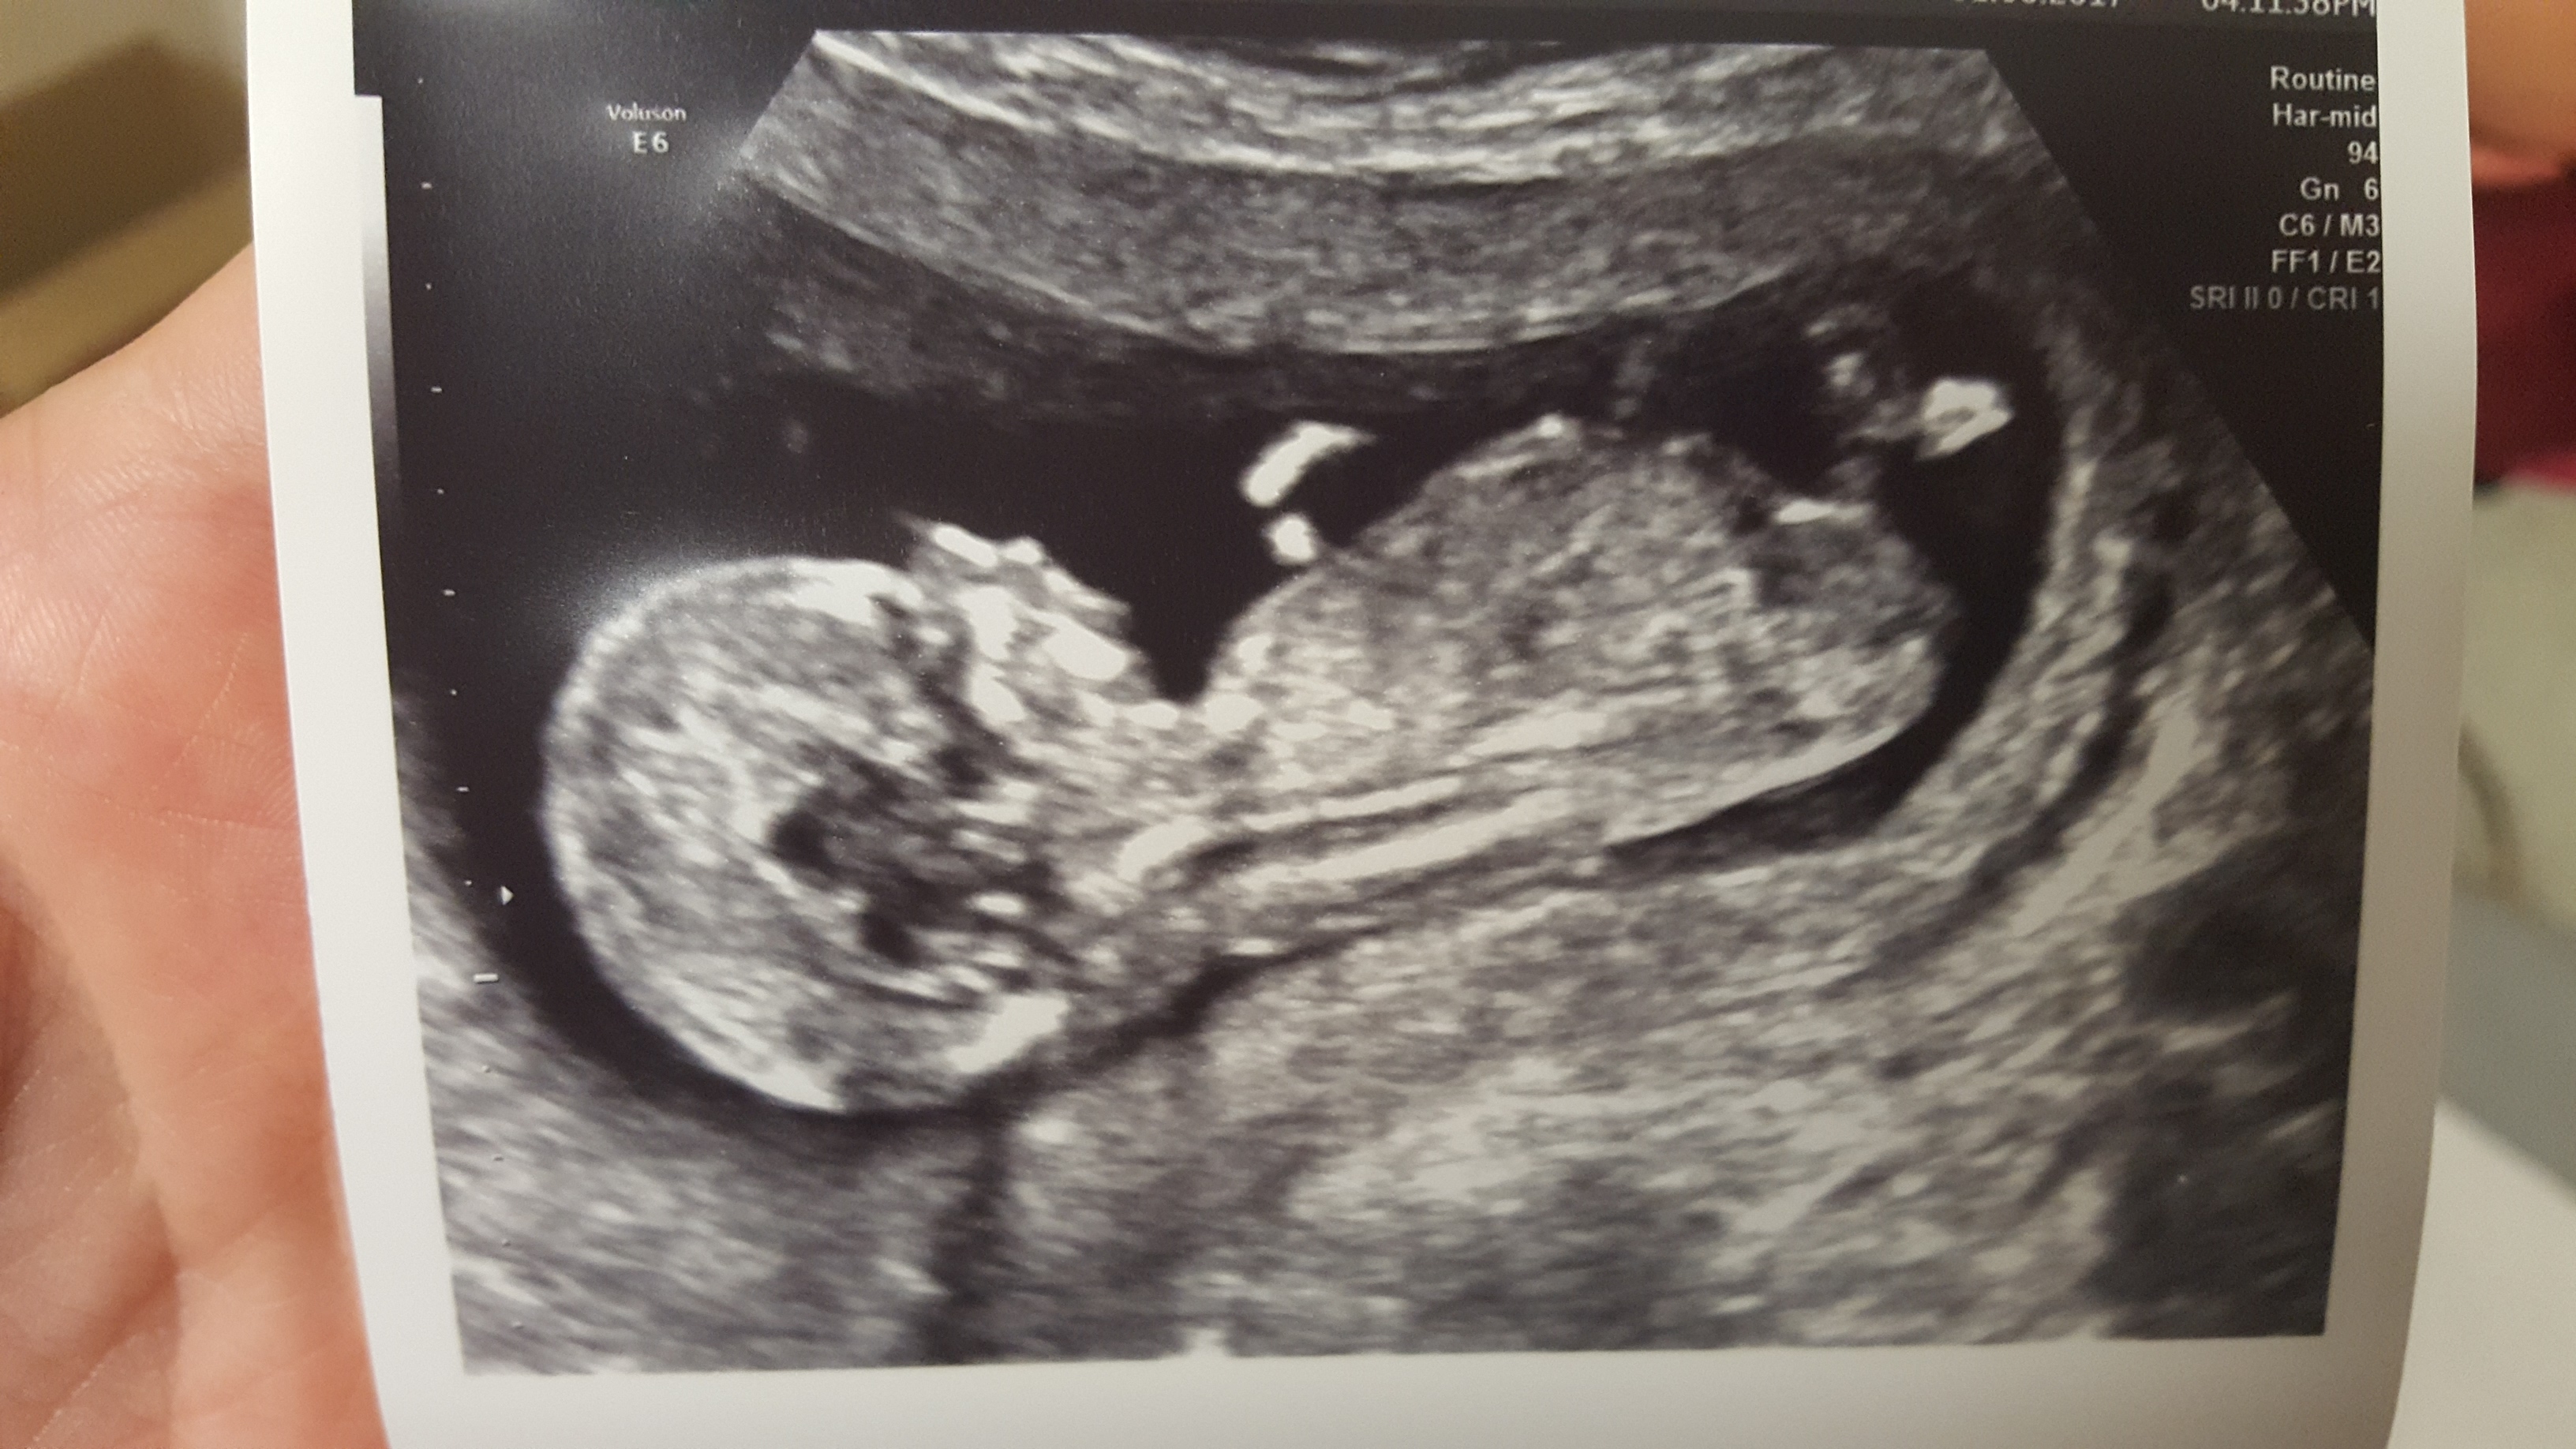

Had my scan yesterday 13+4 any idea what it could be? I'm usually good but lost on this one

Girl lean from the last pic. Not terribly confident though- I'd say 60/40.

Thank you. The nub seems to be pointing downwards which confused me but I leaning pink

I'm going boy as that looks like stacking in the first two pictures, only 60:40 to blue though...